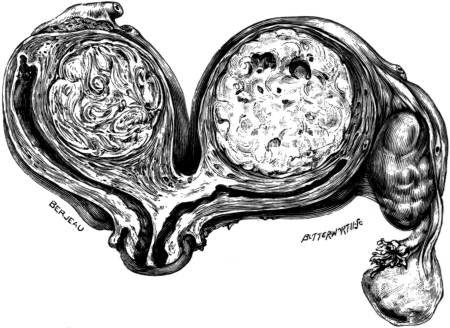

| 2. | Secondary Cancer of the Ovary in Section | 15 |

| 4. | A Tuberculous Fallopian Tube and Ovary: Entire and in Section | 24 |